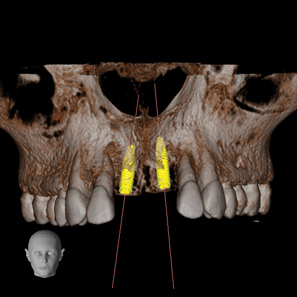

Fig 2. CBCT images show axial (Fig 2) and cross-sectional (Fig 3) views, and 3D reconstruction view (Fig 4) with virtually planned implant Nos. 8 and 9.

Figure 2

Fig 3. CBCT images show axial (Fig 2) and cross-sectional (Fig 3) views, and 3D reconstruction view (Fig 4) with virtually planned implant Nos. 8 and 9.

Figure 3

Fig 4. CBCT images show axial (Fig 2) and cross-sectional (Fig 3) views, and 3D reconstruction view (Fig 4) with virtually planned implant Nos. 8 and 9.

Figure 4